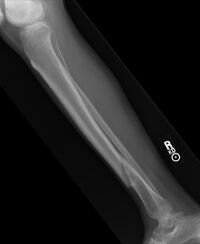

Gebrochenes Schienbein

Ruhigstellung, Schienung, anschließend Transport ins Krankenhaus. Da die betroffene Stelle auf keinen Fall belastet werden sollte, empfiehlt sich der Abtransport der betroffenen Person mit einer Trage. Im Falle einer Ohnmacht oder einer möglichen Wirbelsäulenverletzung darf der Abtransport nur durch Fachleute (Sanitäter, Notärzte) vorgenommen werden.

Mit Hilfe einer Röntgenaufnahme wird der Schweregrad der Verletzung abgeklärt. Es erfolgt entweder eine Behandlung mit Gips oder eine operative Versorgung. In der Rehabilitation unterstützen Mobilisations-, Kräftigungs-, Koordinations- und Ausdauerübungen den Heilungsprozess wesentlich. Die volle sportliche Belastbarkeit ist, je nach Bruchart, erst nach vielen Wochen der völligen Bruchheilung gegeben.